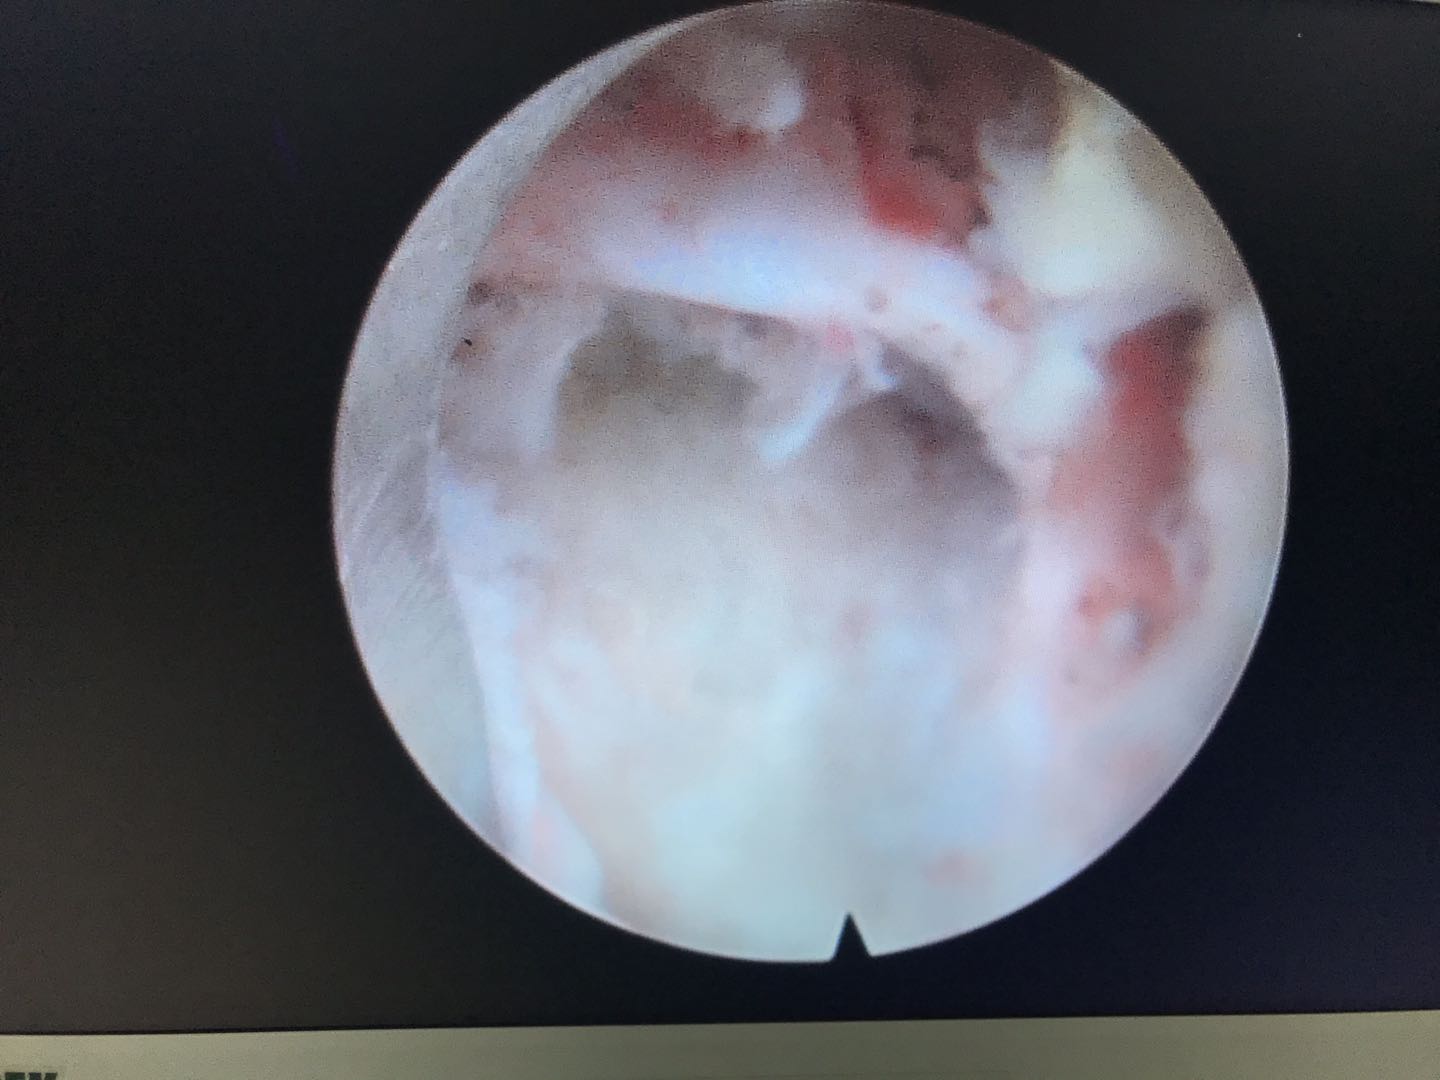

经过1小时的努力,胜利完成了手术!老奶奶的腰痛得到缓解!进行直腿抬高试验70阴性,加强试验阴性!